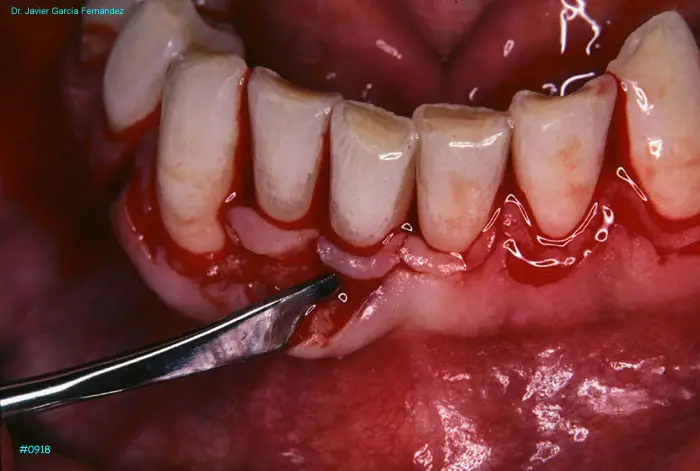

Atlas of Surgical Techniques in Periodontics. Chapter III. Atlas de Técnicas Quirúrgicas en Periodoncia